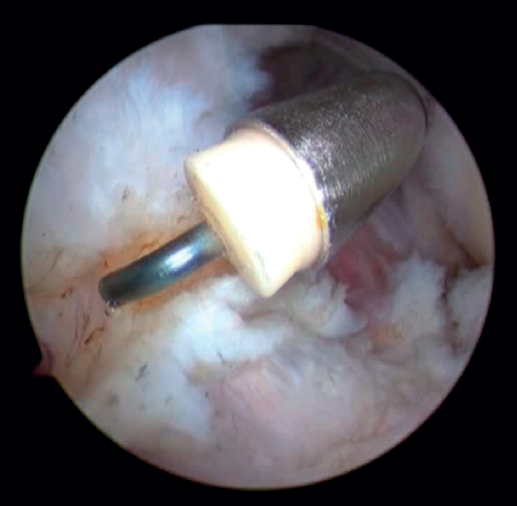

Una vez realizado el tratamiento en el compartimento posterior, realizaremos el portal proximal medial (o anteromedial), unos 2 cm proximales al epicóndilo medial y anterior al septo intermuscular medial, por donde introduciremos el trocar en dirección a la cabeza radial por delante del húmero. Una vez identificadas las estructuras articulares, realizamos bajo visión directa el portal anterolateral con técnica de fuera a dentro aproximadamente 1 cm proximal y 1 cm anterior al epicóndilo lateral(24). En este momento, se debe realizar la exéresis de los cuerpos libres, la sinovectomía, la eliminación de las adherencias tisulares y la exéresis de los osteofitos en caso de que fuera necesario. Una vez hecho esto, quedaría realizar la capsulotomía. Se puede hacer de medial a lateral o viceversa, con vaporizador o pinza de tipo basket. La preferencia de los autores es realizarla 1 cm proximal a la punta de la coronoides y anterior a la cúpula radial, de lateral a medial y usando un vaporizador de tipo hook o “gancho” (Saber 30®, Smith & Nephew) (Figura 5) que añade precisión en la profundidad del corte para evitar lesionar estructuras neurovasculares próximas a la cápsula articular. Una vez completada la capsulotomía anterior, se aprecia el tejido muscular del músculo braquial (Figura 6).